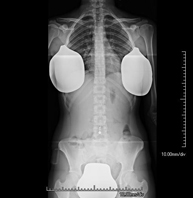

- Telerradiología columna

Técnica mediante la cual, utilizando rayos X, se obtienen imágenes de toda la columna vertebral para su estudio, valorando especialmente la presencia de escoliosis y dismetrías pélvicas.